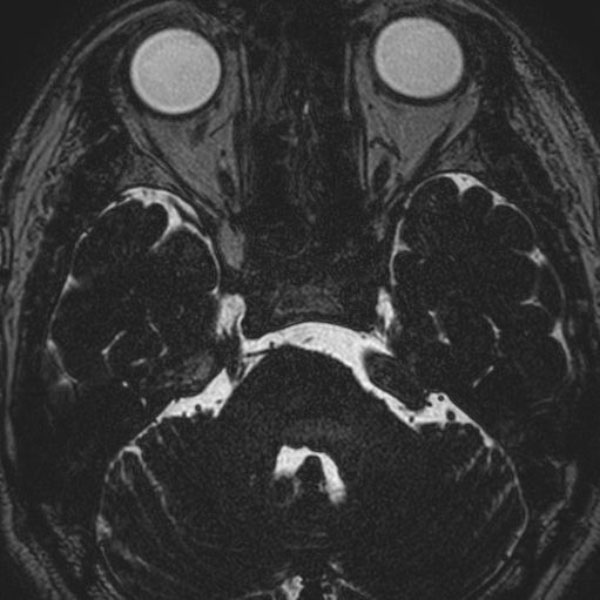

手術前

(MR1)